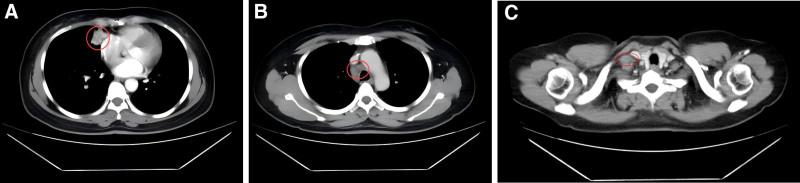

Chest computed tomography revealed a 35 mm × 31 mm mass in the right middle lung with enlarged supraclavicular and mediastinal lymph nodes. A biopsy confirmed the diagnosis of SCC. Staging was determined as cT3N3M1a (stage IVA), and genetic testing revealed no actionable driver mutations, while PD-L1 expression was 30% (tumor proportion score).

胸部计算机断层扫描显示右中肺有一个35毫米×31毫米的肿块,锁骨上和纵隔淋巴结肿大。活检确诊为SCC。分期确定为cT3N3M1a(IVA期),基因检测未发现可操作的驱动基因突变,而程序性死亡受体配体1(PD-L1)表达为30%(肿瘤比例评分)。